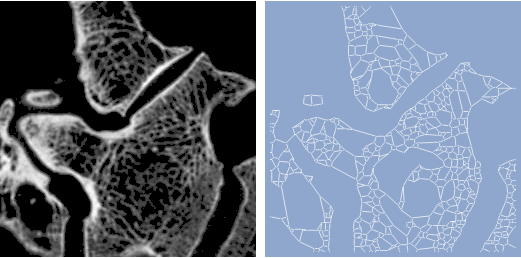

Construir un grafo de una estructura de hueso trabecular usando la función

MorphologicalGraph

en

Mathematica

8.

graph = MorphologicalGraph[ ColorNegate[Image[WatershedComponents[image]]], GraphStyle -> "BackgroundBlue", ImageSize -> {256, 256}];

Row[{image, Spacer[9], graph}]

Out[3]=